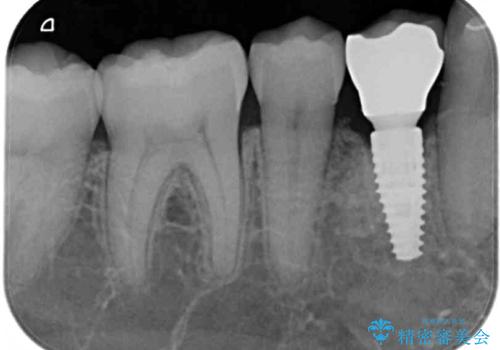

下顎は左右1本ずつ小臼歯が欠損しており、右側にはやや大きな欠損がありました。

欠損により下顎歯列は相対的に小さく、上顎に深く咬みこんでしまうディープバイトとなっていました。

インプラントの埋入は矯正治療中に行い、矯正治療後はインプラント上補綴および、前歯のセラミック治療を行いました。